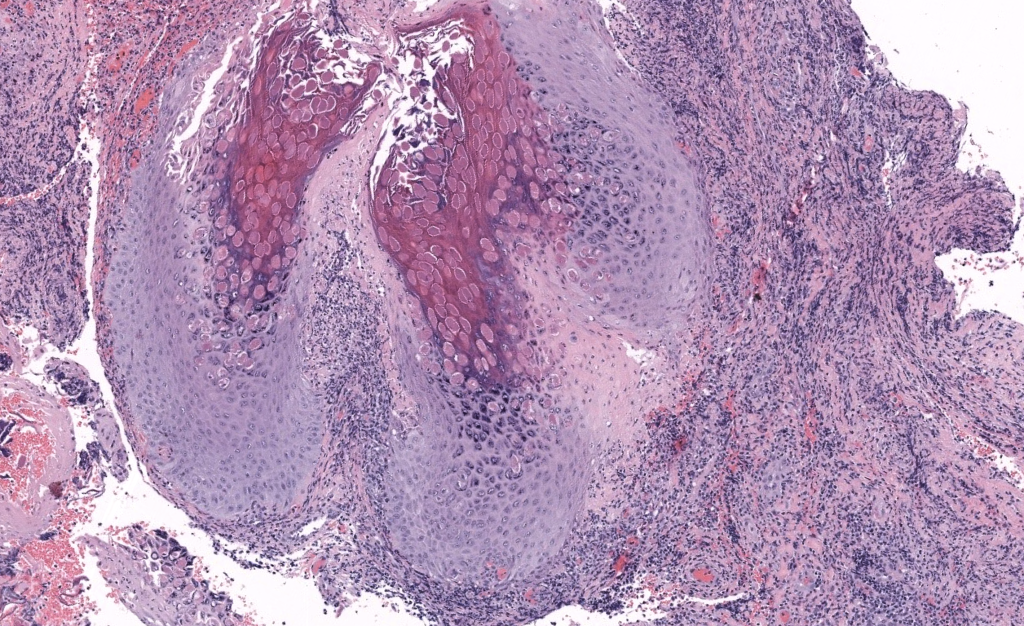

- Patrón: proliferación epidérmica endoexofítica en lóbulos con cráter central.

- Claves diagnósticas: cuerpos de Henderson–Paterson (inclusiones eosinofílicas citoplasmáticas en queratinocitos suprabasales a granulares; desplazamiento nuclear periférico).

- Tinciones/IF/IHQ: no requeridas de rutina; inclusiones se ven en H–E. Diferenciar de Cryptococcus(mucicarmín‑positivo) si duda infecciosa fúngica.

- H–E muestra cuerpos de Henderson–Paterson; raramente se necesitan estudios especiales.